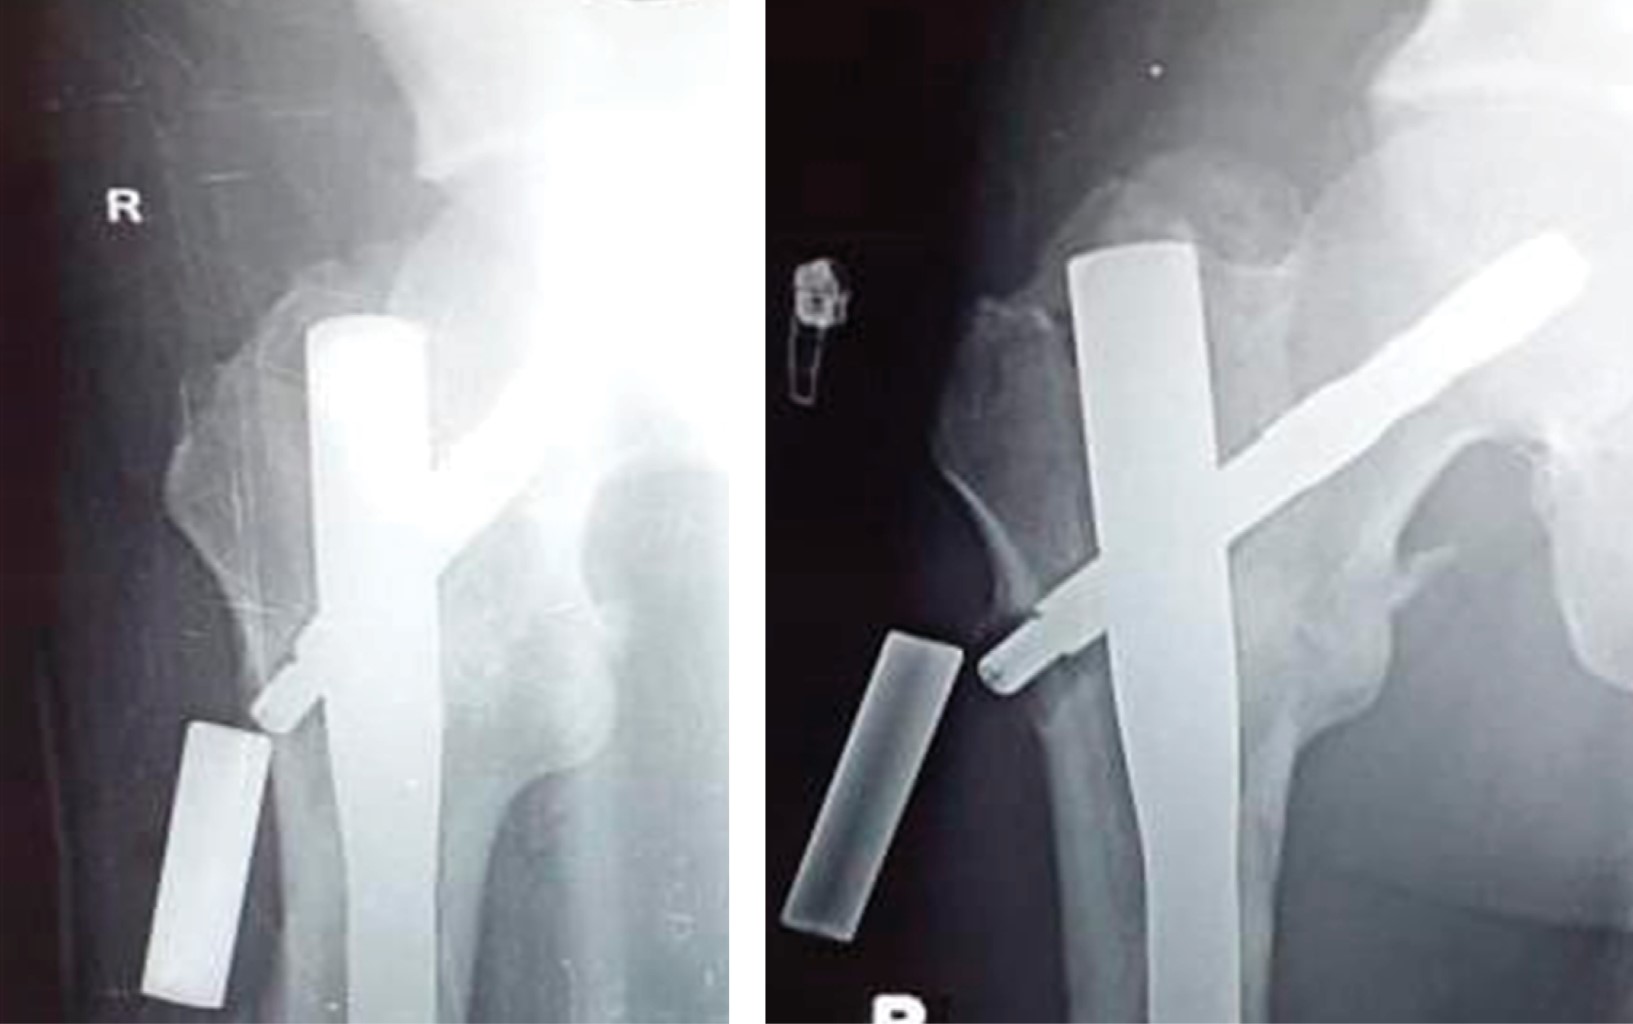

Implant related complications like screw back out (Figure 1), guide wire breakage (Figures 2 and 3), Z effect (Figure 4), TAD outliers (Figure 5) were more in PFN group whereas lateral screw protrusion, locking mechanism failure and barrel disengagement was more in PFNA2 group as shown in Figures 6, 7, 8 and 9. Neck shaft valgus outliers are more common in PFN group (Figure 10).

Implant-related complications, such as screw back-out, guidewire breakage, and proximal protrusion, were more pronounced in the PFN group, whereas lateral screw protrusion and medial migration were notable in the PFNA2 group.24 Lateral screw protrusion was observed in four patients in the PFNA2 group and one patient in the PFN group at the final follow-up in our study. Hu et al suggested a morphological mismatch in the Asian population between the proximal fragment of PFNA2 and the greater trochanter, leading to post-operative lateral trochanter pain.24